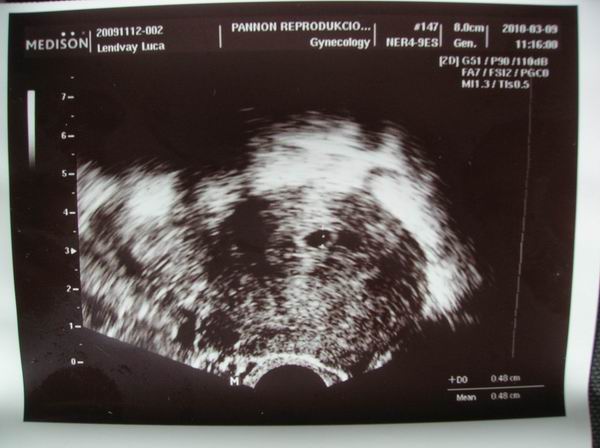

Láttuk a babót!!! :lol: 5 mm-es petezsák! :lol:

Jövő hét péntek szív-uh.

Még annyi, hogy a baba mellett látott a doki valami bevérzést, de reméljük az nem okoz majd semmi gondot. Kérdezte véreztem-e, mondtam nem. Javasolta, hogy emeljük az utrót 2x2-re, mondtam, hogy azon már túl vagyunk, de innentől akkor 3x2-őt fogok dugni.

És íme Ő (a fekete pötty, középtájon):

Megjártuk a BMC-t, van egy 5mm-es embriócskánk szívpulzálással. Nagyon boldogok vagyunk.